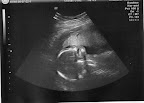

In December, Deven will have a little...

...brother!

(Yes, the image on the left is looking up the baby's backside as if he's on his knees...and yes, that's his "lulloo" as they'd call it in Hindi). Click on the photos to see larger versions.

He's healthy, and spent the entire Ultrasound spread-eagle; but with his arms crossed over his heart. So, I have to go back next week, because the ultrasound tech needs to see more of his heart, to confirm 'all systems go.' So far, so good - but I'm glad they're making me go back.